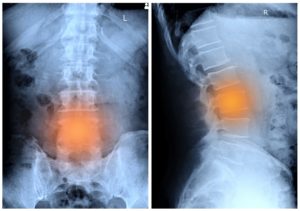

The underlying causes of lower back pain when walking can be complex. Lower back pain is often the result of a relationship of risk factors. Exploring the most commonly involved…